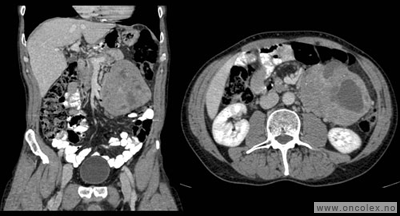

• CT toraks, buk og bekken er standard utredningsmetode ved svulst i buken og på bakre bukvegg, og kan gjøres ved lokalsykehus. De viktigste fordelene ved CT er at undersøkelsen tar kort tid. Innføringen av spiral-CT, og spesielt multislice-teknikk, har forbedret kvaliteten. Røntgen av lungene er som regel tilstrekkelig for å oppdage eller utelukke spredning til lunge.

• MR. Selv om CT foretrekkes når det gjelder buk og bekken, er MR ypperlig tilleggsundersøkelse for å vurdere svulster i bekkenet. Mens pasientens bevegelser reduserer bildekvaliteten av buken og til en viss grad bakre bukvegg, kan MR av bekken være til stor hjelp for å definere omfanget av sykdommen og for å fastsette riktig diagnose i bekkenet.

Typiske funn

Bildeeksempler